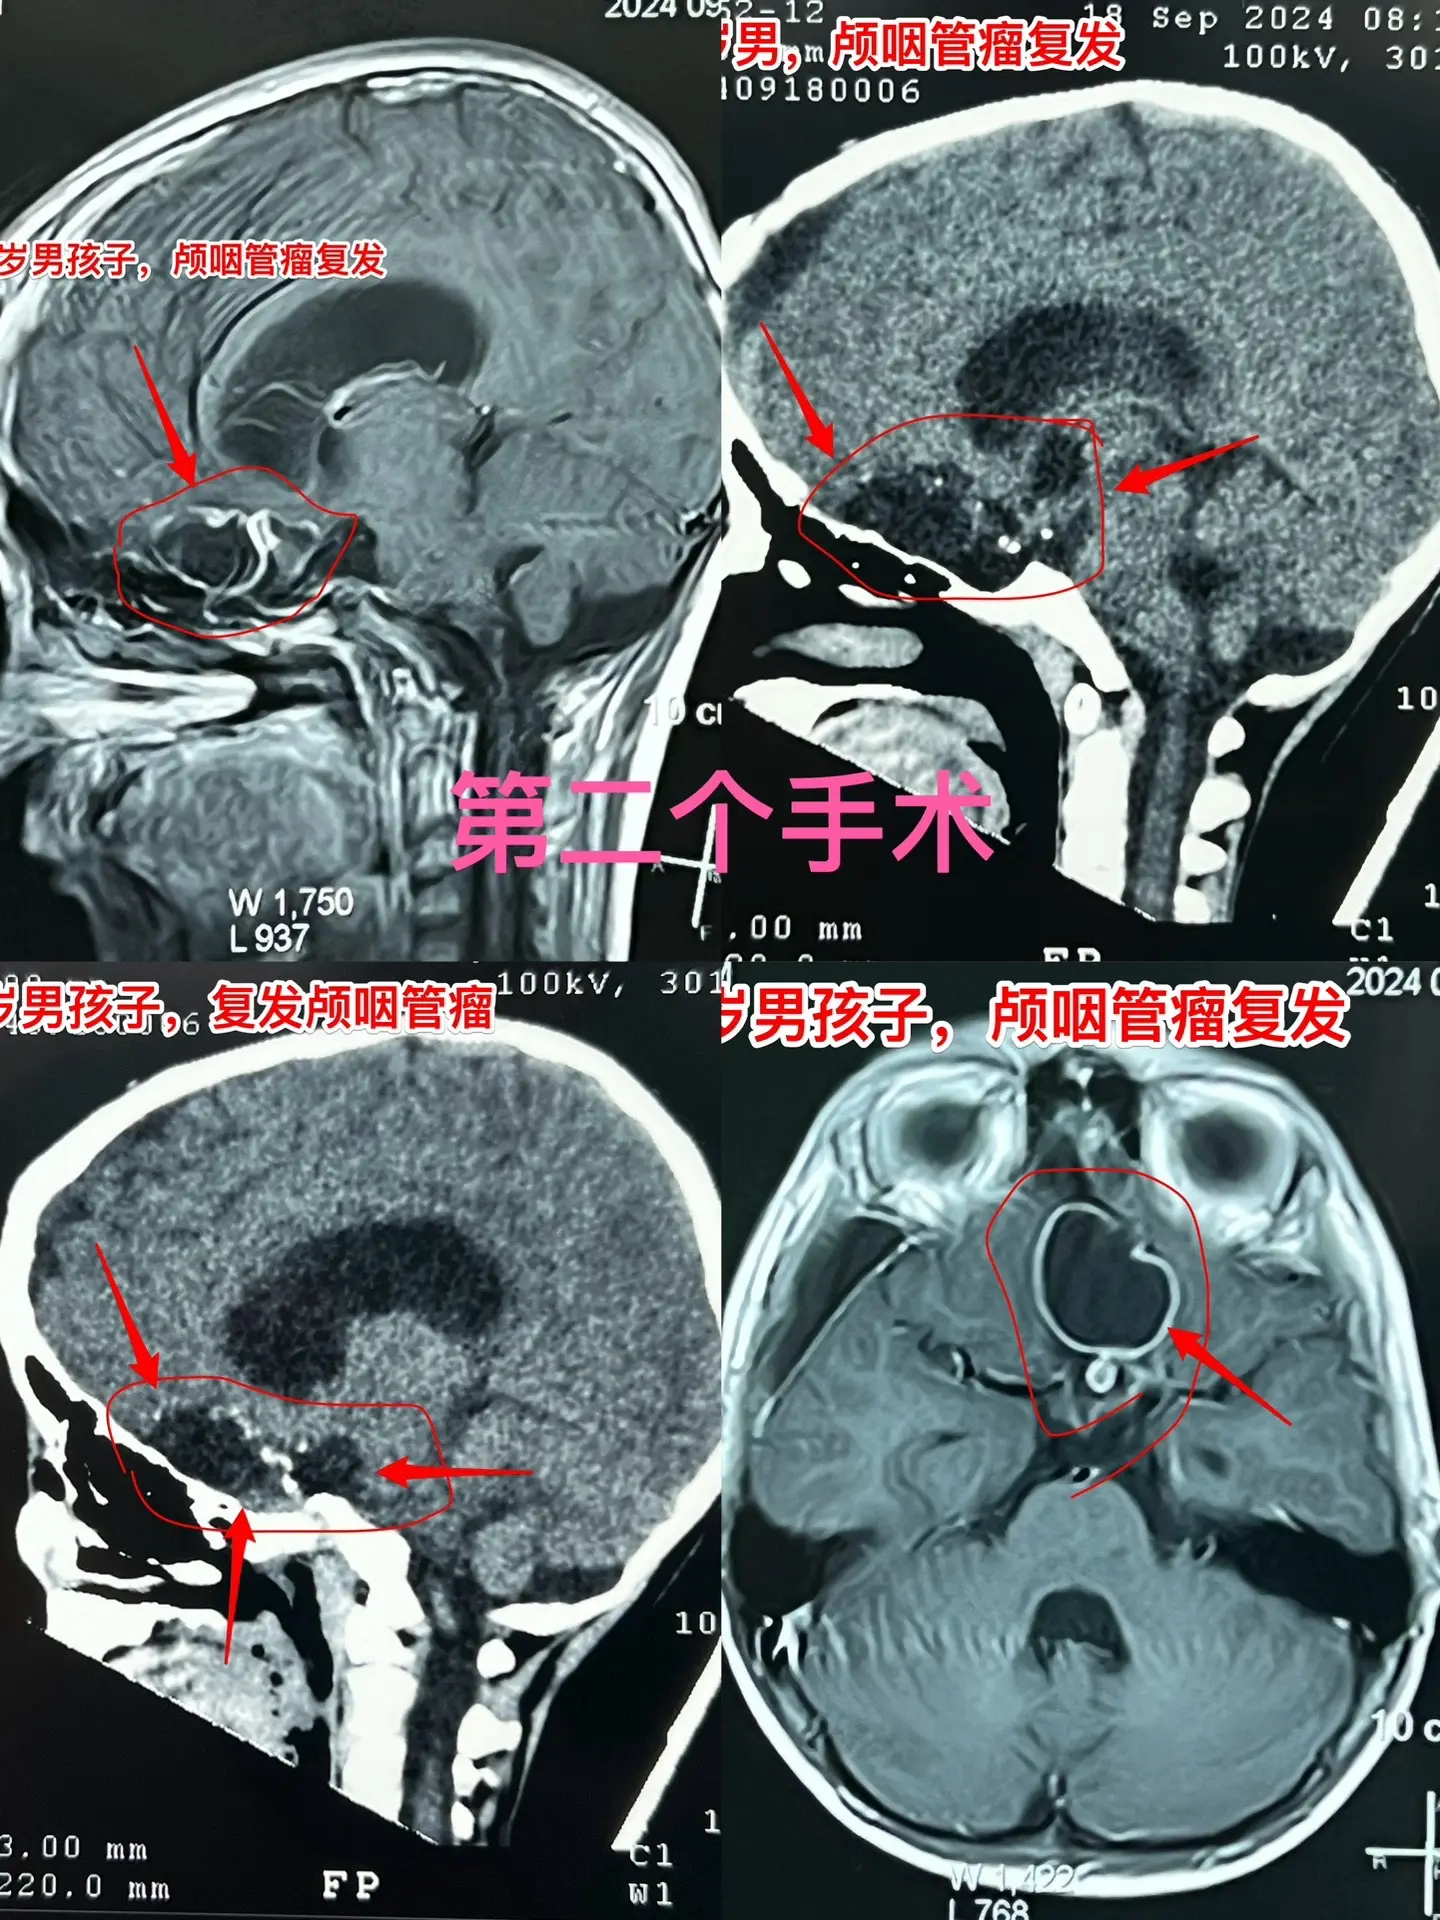

今日两个颅咽管瘤手术。1,6岁男孩子,安徽宿州人。2023年5月因视力...

一天完成两个颅咽管瘤手术几乎成了常态。今天的两个颅咽管瘤手术,强度很大...

昆明男孩在14个月时间内两次大手术。昆明的8岁男孩子,2023.3在昆...